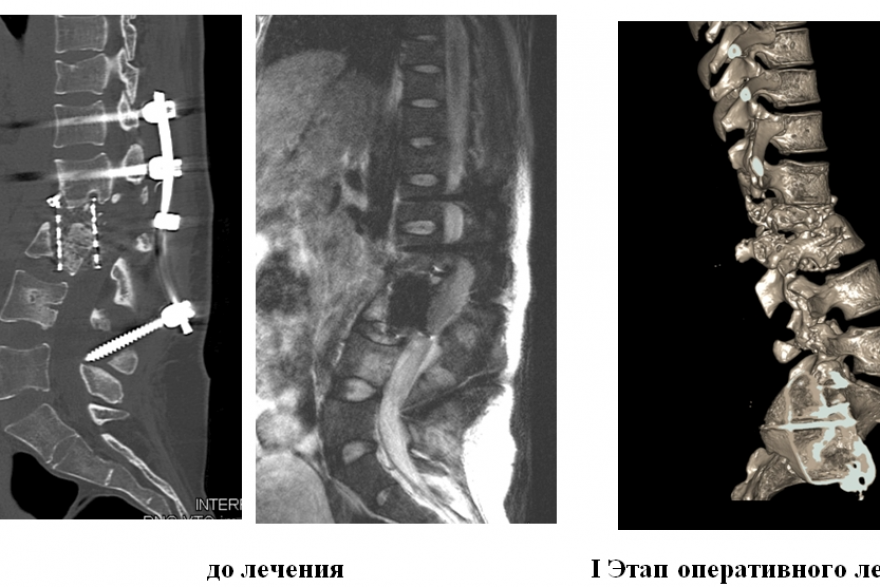

26-летняя жительница Кемерово в 2020 году, упав с многоэтажного дома, сломала таз и позвоночник. Первые операции сделали в Москве и в Новосибирске, однако спустя полгода начался остеомиелит позвоночника на фоне перипротезной инфекции.

Из-за воспалительного процесса, а также из-за того, что установленный имплант проник в область позвоночного канала, женщину могло парализовать, отмечают в пресс-службе Центра Илизарова. В таком состоянии пациентку доставили в Клинику костно-суставной инфекции в Курган.

- Первым этапом мы удалили старую конструкцию из заднего доступа, далее спустя две недели мы установили новую конструкцию, потом взяли пациентку на третий более сложный ревизионный этап со стороны живота. Удалили ей большой сетчатый имплант, который мигрировал в область позвоночного канала, расширили область декомпрессии и установили новый. Риск операции заключался в том, что при удалении импланта важно было не повредить спинной мозг, - прокомментировал руководитель группы гнойной вертебрологии Центра Илизарова, врач-нейрохирург Максим Древаль.

Девушке провели сложную ревизионную операцию. Спустя 2,5 месяца комплексного лечения жительница Кемерово вернулась домой. Рана полностью зажила, воспаление прекратилось, а главное, девушку удалось активизировать, отмечают в пресс-службе Центра.